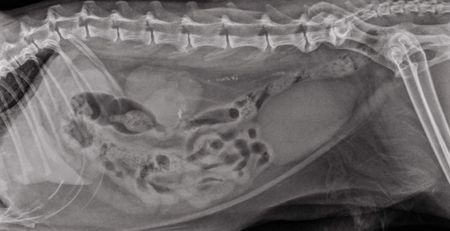

Much can be learned about the gastrointestinal tact (GIT) by careful evaluation of survey abdominal radiographs. Survey radiographs of the abdomen in cases of GIT disease should always include the stomach, liver, and diaphragm. Stomach position, size, shape and contents are evaluated. The small intestine is assessed for position and distribution within the abdominal cavity, diameter, and luminal contents.